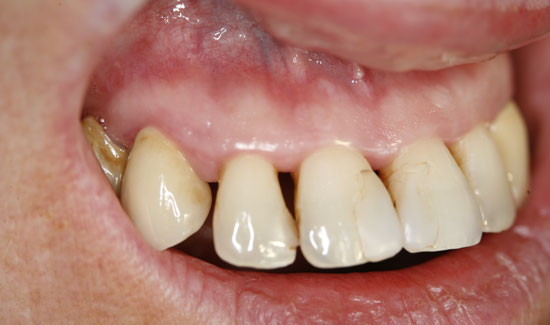

Die Patientin stellte sich in unserer Praxis vor mit der Frage der konservativen Erhaltbarkeit der Oberkieferfrontzähne bei chronischer Parodontitis. Wir fanden generalisierte Taschenbildungen (> 10 mm), Spontanblutungen und einen Lockerungsgrad 2/3, d.h. extraktionswürdige Zähne. Als Überbrückungsmaßnahme (Feiertagssituation) bis zu Sanierungsmaßnahmen boten wir ihr lokale Ozongasbehandlungen an.

Dokumentation des Falles:

Abb. 2: Klinischer Aspekt der Regio 12, Entstehung von Gasblasen am entzündeten Gewebe. Fortlaufende Absaugung in der Nähe des Einsatzgebietes